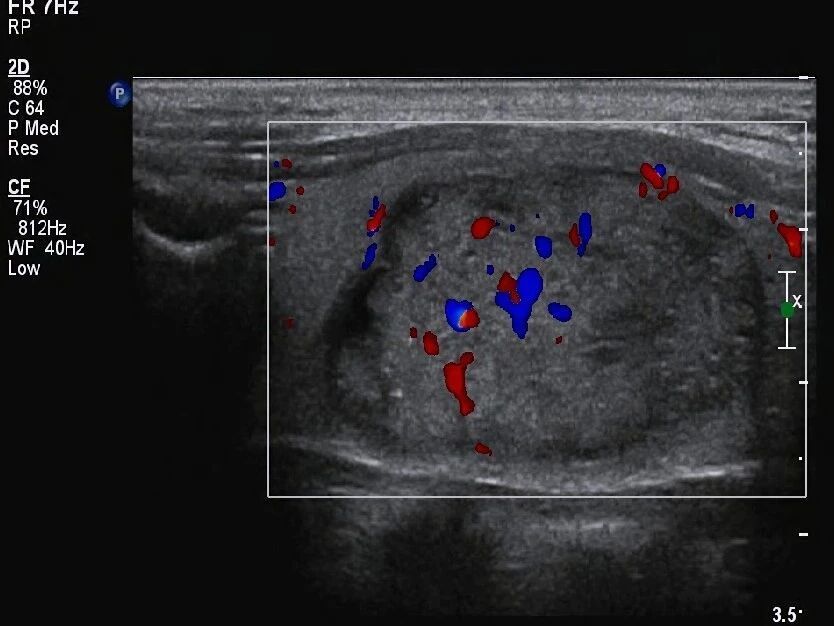

在甲状腺超声里,有好些小于1毫米的亮点,这些亮点有隐藏重要信息的可能,这些叫做点状强回声,有时这些点状强回声后方带着呈逐渐减弱态势的平行线条,样子类似彗星尾巴,这种情况通常是浓缩胶质形成的混响伪像,然而实际诊断时,医生常碰到既无声影又无可观察彗尾征的强回声点,这时判断其性质就特别困难了。

点状强回声存在,其性质不同,处理有明显差异,浓缩胶质一般代表良性,微钙化算得上是恶性指征,有研究表明,在恶性结节中微钙化出现的频率,比良性结节显著高些,这就是医生对这些小点十分重视的原因 。

点状强回声出现,其后方伴有声影,这属于典型的微钙化表现,多条平行强回声存在,向深部延伸,这是由浓缩胶质形成的彗星尾伪像,然而在临床实践当中,这两种特征并非总是如此典型,小于1毫米的微钙化,可能不会产生明显声影,给准确判断造成了难度 。

专家们给出建议,处理这类情况要采取谨慎原则,针对结节内出现性质不明的点状强回声,应优先考虑微钙化的可能性,这种处理方式虽可能带来增加不必要穿刺检查的情况,却能够有效降低漏诊恶性肿瘤的风险。?

点状强回声的位置意义

结节在不同部位,那里出现了然点状强回声,而其临床意义有着截然不同的情况, 在位于囊性部分的体现为短线状强回声,尤其是伴有典型彗尾征的那种,大多是由浓缩胶质形成的,这属于良性表现,这些胶质实际上是甲状腺滤泡内浓缩的胶状性质物 。

点状强回声出现在实性部分时,此显示情况下其后方没有清楚明显的彗尾征,这时需十分密切高度警惕微钙化存在的可能性,在这样的状况下,即便结节其他特征表现展示良好,也应按可疑特征样式处理应对,还建议更进一步深入检查明确定性质,。